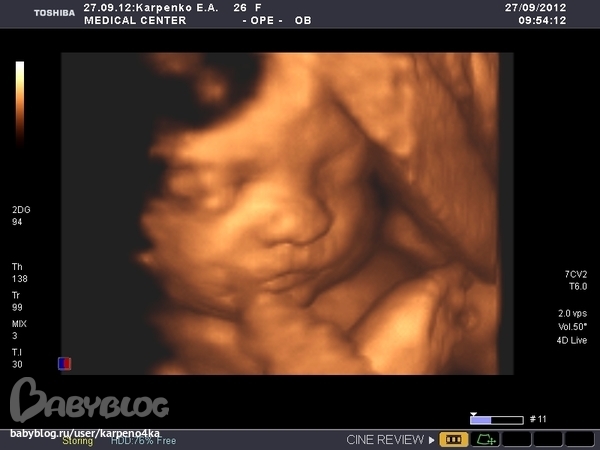

Красотища, завораживает аж. Там всевнутри таинственно. До чего техника дошла.

Какая лапочка.......В нашем городе нет 3d:(на 12ой неделе в другом городе делали только,но там еще мало что видно было,а на вашем сроке бы сделать было бы классно:)))))Супер просто...такая память,еще и фото такое удачное...

у нас видео 3D записывают только на последнем узи, а фотки можно хоть с первого узи 3D делать) в 20 недель я делала еще, но там еще скелетик просвечивался, а ща то пухляшка уже)